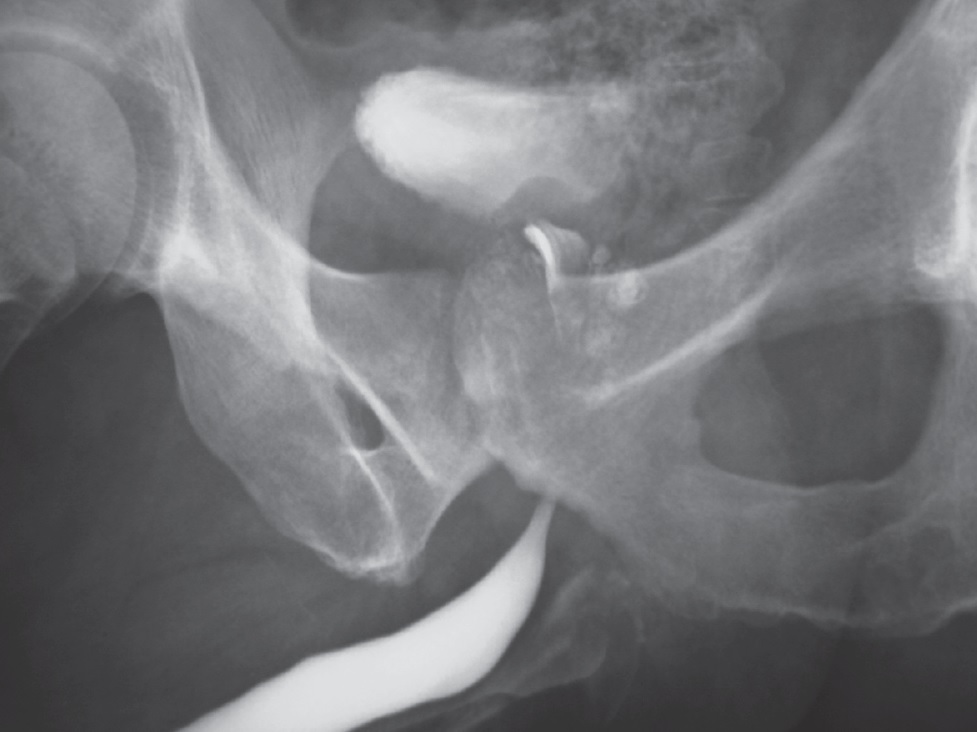

При осмотре: нормального телосложения, удовлетворительного питания. В скротальных органах патология пальпаторно не определяется. Пальцевое ректальное исследование: ампула свободна. Простата увеличена в размере, бугристая, плотная, умеренно болезненная; бороздка сглажена. Температура тела нормальная. В общем анализе крови лейкоцитоз 8,6 · 106, СОЭ 47 мм/час, в остальном — в пределах нормальных величин. Трехстаканная проба мочи: в первой порции лейкоцитов 17–20 в поле зрения, во второй — 5–7, в третьей порции лейкоцитов до 40 в поле зрения. В секрете простаты, полученном путем массажа, лейкоцитов 80–100, в эякуляте, полученном путем мастурбации, — 2,7 млн в 1 мл. Ретроградная уретрография с контрастом — затеки в каверны предстательной железы (рис. 1).

Рис. 1. Каверны предстательной железы